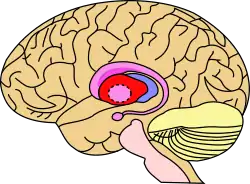

Putamen (in red) shown within the brain | |

The putamen (/pjutˈeɪmən/; from Latin, meaning "nutshell") is a round structure located at the base of the forebrain (telencephalon). The putamen and caudate nucleus together form the dorsal striatum. It is also one of the structures that compose the basal nuclei. Through various pathways, the putamen is connected to the substantia nigra, the globus pallidus, the claustrum, and the thalamus, in addition to many regions of the cerebral cortex. A primary function of the putamen is to regulate movements at various stages (e.g. preparation and execution) and influence various types of learning. It employs GABA, acetylcholine, and enkephalin to perform its functions. The putamen also plays a role in degenerative neurological disorders, such as Parkinson's disease.

The putamen is a structure in the forebrain. Along with the caudate nucleus it forms the dorsal striatum. The caudate and putamen contain the same types of neurons and circuits – many neuroanatomists consider the dorsal striatum to be a single structure, divided into two parts by a large fiber tract, the internal capsule, passing through the middle. The putamen, together with the globus pallidus, makes up the lentiform nucleus. The putamen is the outermost portion of the basal ganglia. These are a group of nuclei in the brain that are interconnected with the cerebral cortex, thalamus, and brainstem. Basal ganglia include the dorsal striatum, substantia nigra, nucleus accumbens, and the subthalamic nucleus.